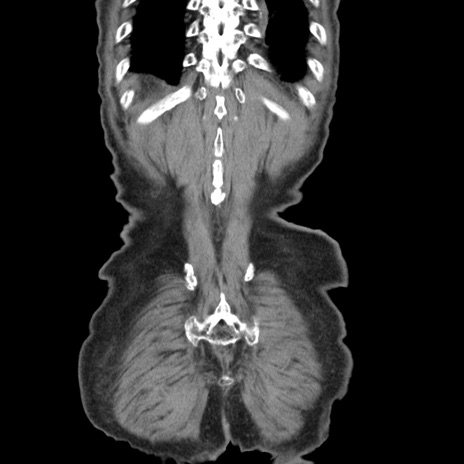

矢状断像